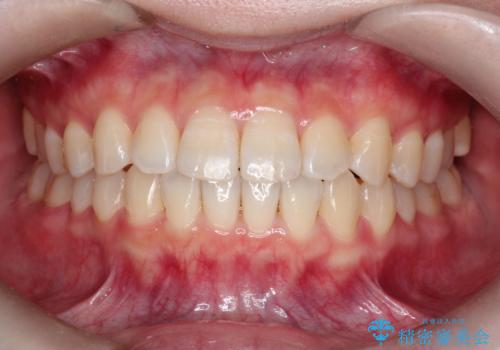

前歯と奥歯のガタガタを矯正で改善

- 患者様は、前歯と奥歯のガタガタ(叢生)を改善し、正面から見た時の歯並びを美しく整えたいとのご要望で来院されました。診断の結果、非抜歯での矯正が可能と判断し、インビザラインを使用する治療計画を立案しました。透明な矯正装置で目立ちにくい治療を行いながら、前歯と奥歯の両方を整列させることを目標にしました。

インビザラインを用いて、前歯の見た目を重視しつつ、奥歯のガタガタも改善しました。特に正面から見た際の美しい歯列を意識し、段階的に歯を移動させることで、全体の調和を図りました。治療中は、適切な装着時間を守ることや、装置の清潔を保つことが重要でした。また、歯肉や歯列全体に無理な負担がかからないように移動を管理しながら治療を進めました。結果として、前歯と奥歯がきれいに並び、見た目にも機能的にも満足いただける仕上がりとなりました。